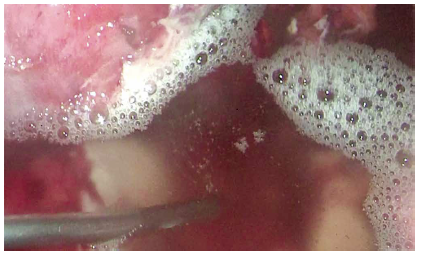

Se solicita una tomografía abdominal que revela una gran colección intraabdominal en el hemiabdomen derecho (Figura 1); se decide la laparoscopía exploratoria en la que se encuentra un absceso gigante intraabdominal de 750 cc (Figuras 2 y 3), que va desde el reborde inferior del hígado hasta el fondo de saco de Douglas. Se toma muestra para cultivo y se drena. Un útero aumentado de tamaño con fibrina en sus paredes, edema y eritema severo en la trompa derecha, revisando con azul de metileno para verificar su permeabilidad. Se encuentra el apéndice cecal en fase necrosada y perforada (Figura 4), el cual se extrae. Posteriormente se realiza el lavado peritoneal con 6.000 cc de solución salina normal (Figura 5). Se deja drenaje en fondo de saco de Douglas (Figura 6). El tiempo de hospitalización y el manejo antibiótico con piperacilina tazobactam fue de 10 días. El reporte del cultivo fue Escherichia coli.